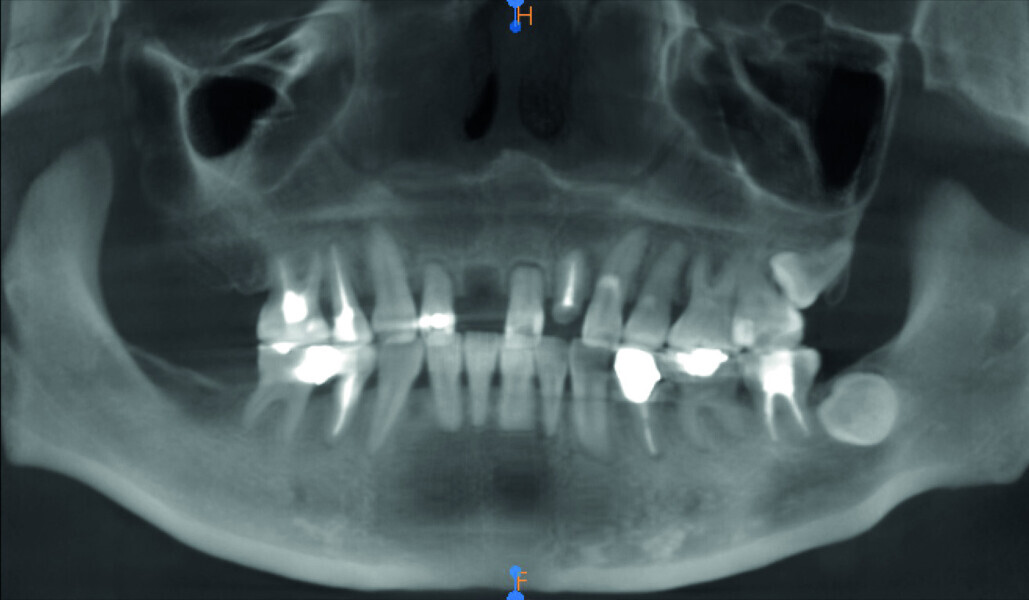

Fig. 3: Pre-op panoramic radiograph.